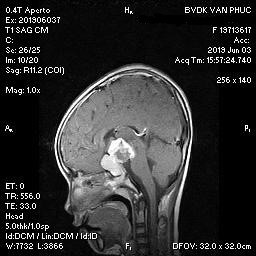

Hình ảnh MRI phát hiện khối u kích thước 27mm x 14mm ở vị trí sọ hầu của bé gái 9 tuổi

Kích thước khối u khá lớn, vị trí tại sọ hầu có xâm lấn xoang hang. Đây là nguyên nhân chính dẫn đến tình trạng sức khỏe suy kiệt, ảnh hưởng thị lực và sự phát triển của bé.